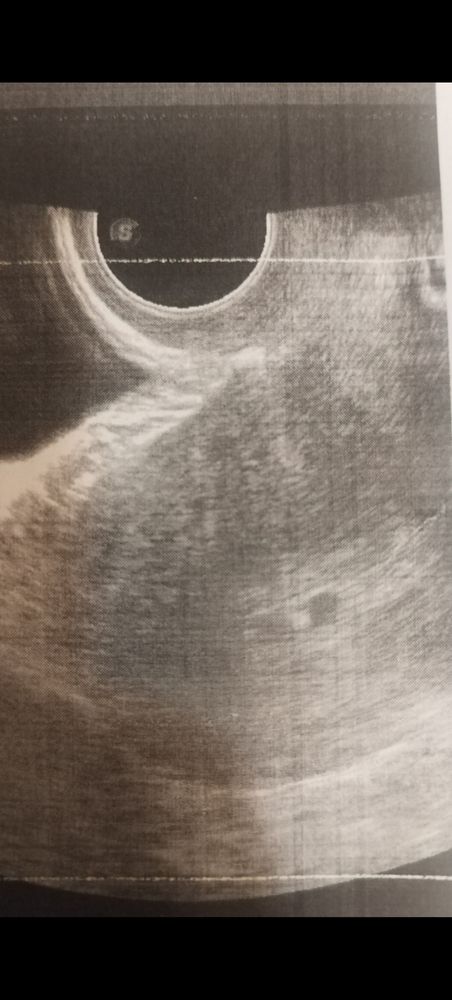

Девочки, так переживаю ..Подскажите, во сколько у вас на узи увидели эмбрионов, сердечки? У меня последние мес.были 6 декабря. По мес.срок 5 недель и 5 дней. Сегодня сходила на узи в надежде увидеть сердцебиение. ( С сыном уже видели в таком сроке. )

Но! Врач не то что сердцебиение не увидел, даже эмбрион не рассмотрел( Под вопросом сказал многоплодная беременность ( правда не знаю, где он там ее рассмотрел). Толком ничего не объяснил, сказал идти к гинекологу . Уже должен же быть эмбрион? Или может быть такое, что позже увидят?

Спасибо! Как бы прожить еще эти 10 дней.. Сейчас нашла в УЗи - в полости матки два образования размером 6мм, что соответствует 5 неделям...